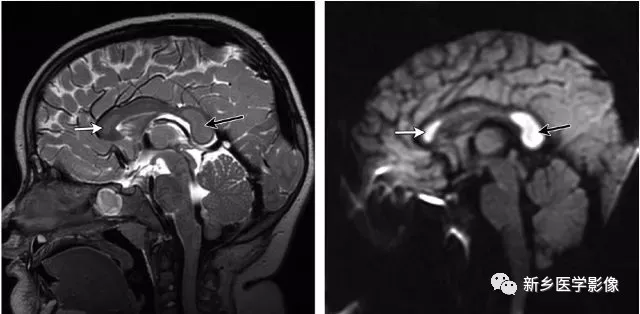

连续酗酒+熬夜 男子出现意识模糊!这些症状千万要警惕确诊为可逆性胼胝体压部综合征。 △董先生的影像结果显示胼胝体压部发生病变(图源:南方科技大学医院) 啥是胼胝体压部综合征? 如果把大脑比作一座城市,胼胝体就是连接左右脑的“跨海大桥”,而胼胝体压部正是桥上的“核心枢纽”。当它因酒精、熬夜或感染...